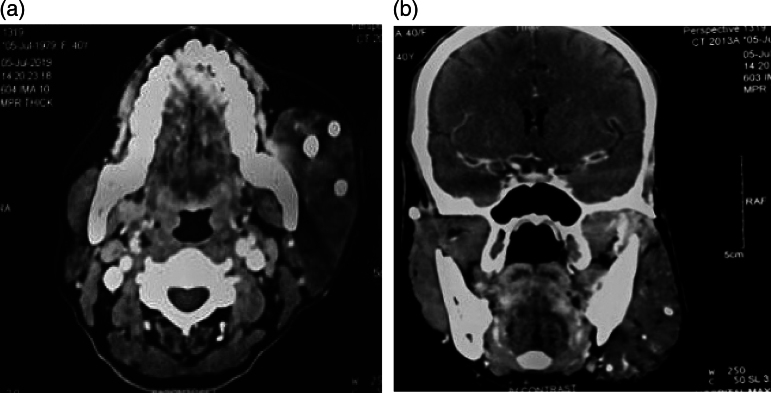

Combined vascular malformation affecting the facial region is an extremely rare clinical entity that is debilitating both functionally and emotionally. Treatment warrants a multidisciplinary approach with the aim of removing the vascular anomalies and ameliorating any functional facial disfigurement. Here, we present a case of a 40-year-old female with combined vascular malformation of the face who was treated successfully with surgical intervention accompanying significant resolution of facial disfigurement.

Abstract Image